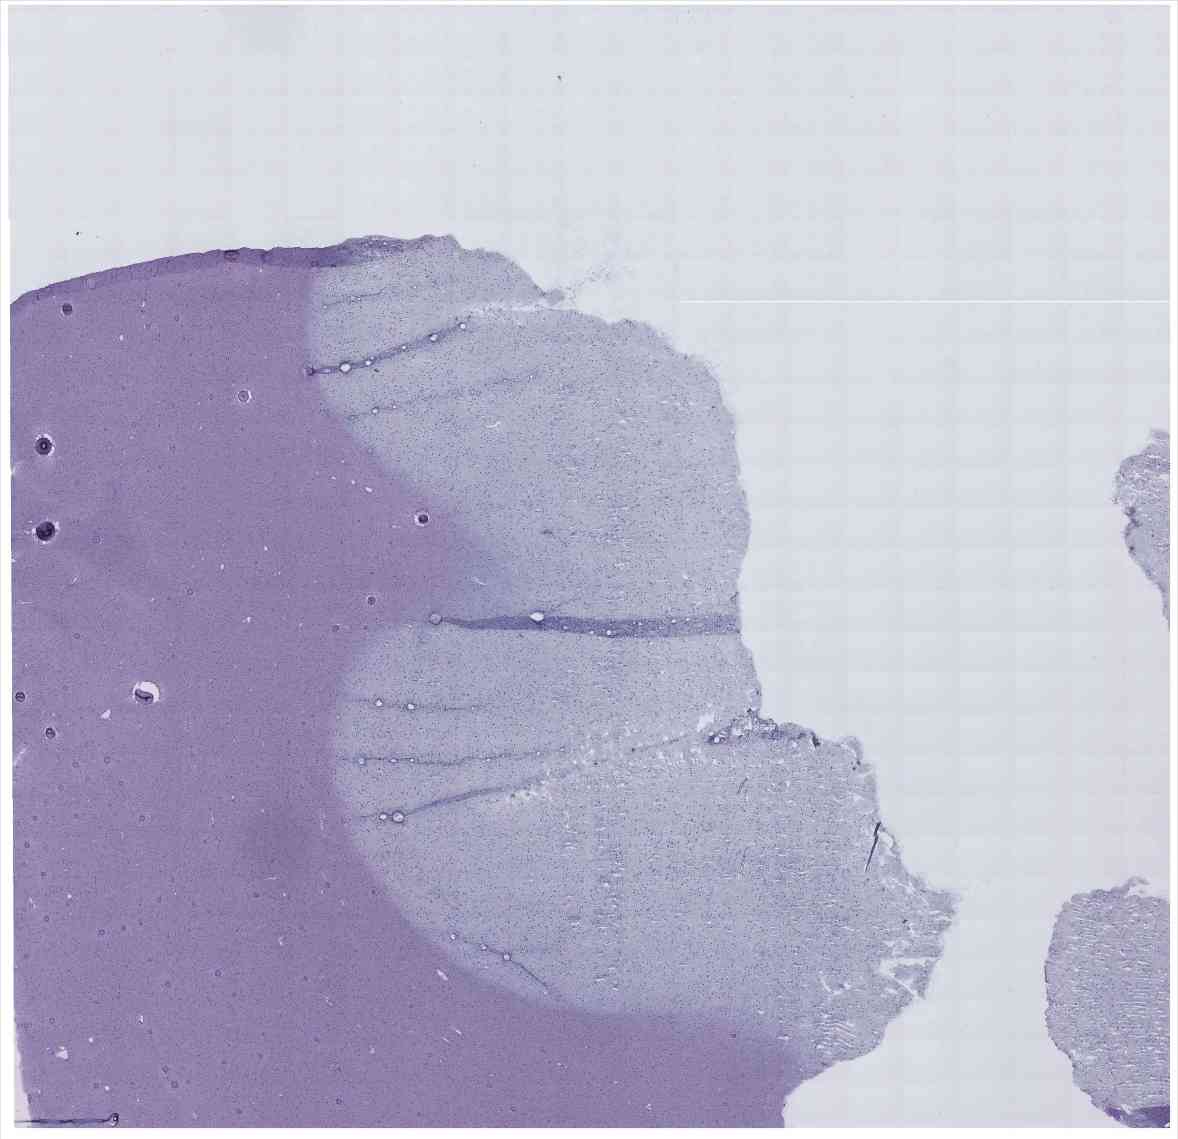

Chip 014 Well C1